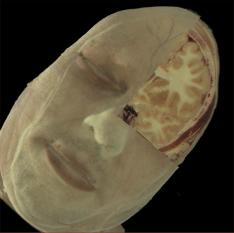

La figura 1‑9 mostra un esempio di surface rendering. Si noti come grazie all’ombreggiatura si avverte la sensazione di tridimensionalità.

Figura 19 Ricostruzione 3D in surface rendering